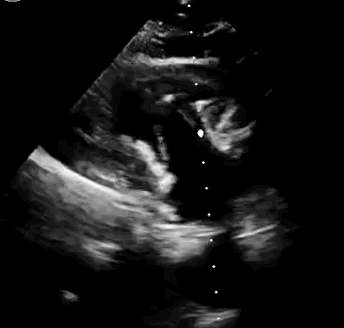

本次臨床前研究經(jīng)右側(cè)頸靜脈置入LuX-Valve Plus輸送系統(tǒng)可調(diào)彎鞘管,在DSA及超聲引導(dǎo)下將人工三尖瓣瓣膜植入到原有三尖瓣位置,利用獨(dú)特的錨定技術(shù)將人工瓣膜支架可靠固定在預(yù)定的位置。

上海中山醫(yī)院葛均波院士、錢菊英院長(zhǎng)、周達(dá)新教授、潘文志教授、潘翠珍教授、李偉教授共同完成此次臨床前研究。術(shù)后葛均波院士對(duì)Lux-Valve Plus的器械操作性能給予了高度評(píng)價(jià),DSA和超聲影像也顯示出在本次研究中Lux-Valve Plus的安全性和有效性俱佳。